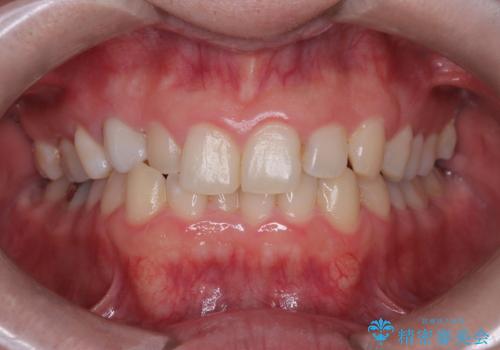

- 下の歯のがたつき(叢生)、真ん中(正中)が右にずれていることを主訴に来院されました。右上前から3番目の永久歯が埋まっている(埋伏)していることから正中は可能な限り合わせることをゴールとしてマウスピースでの矯正治療を選択しました。

今回の矯正治療では、透明なマウスピース型の装置インビザラインを使用しました。がたつきをとるため、安全性が確保できる範囲で歯と歯の間を少し削り必要なスペースを確保しました。